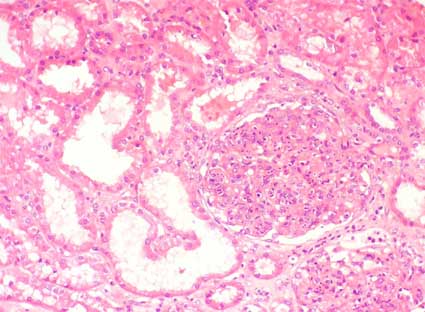

Observe las imágenes de la biopsia

renal.

Figura 1.

H&E, X200.